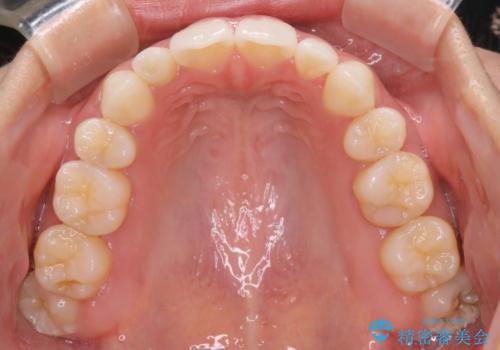

- 口元をさげたいという主訴で来院されました。4番の歯を4本抜歯し、遠心移動とIPRをしました。右上2番が矮小歯のため見た目を重視するならクラウンの提案をしましたが、そのままでの治療を希望されました。

矯正治療の最終段階でスペースクローズにやや時間がかかりましたが、前歯が下がったことで口元の位置も下がりきれいになりました。